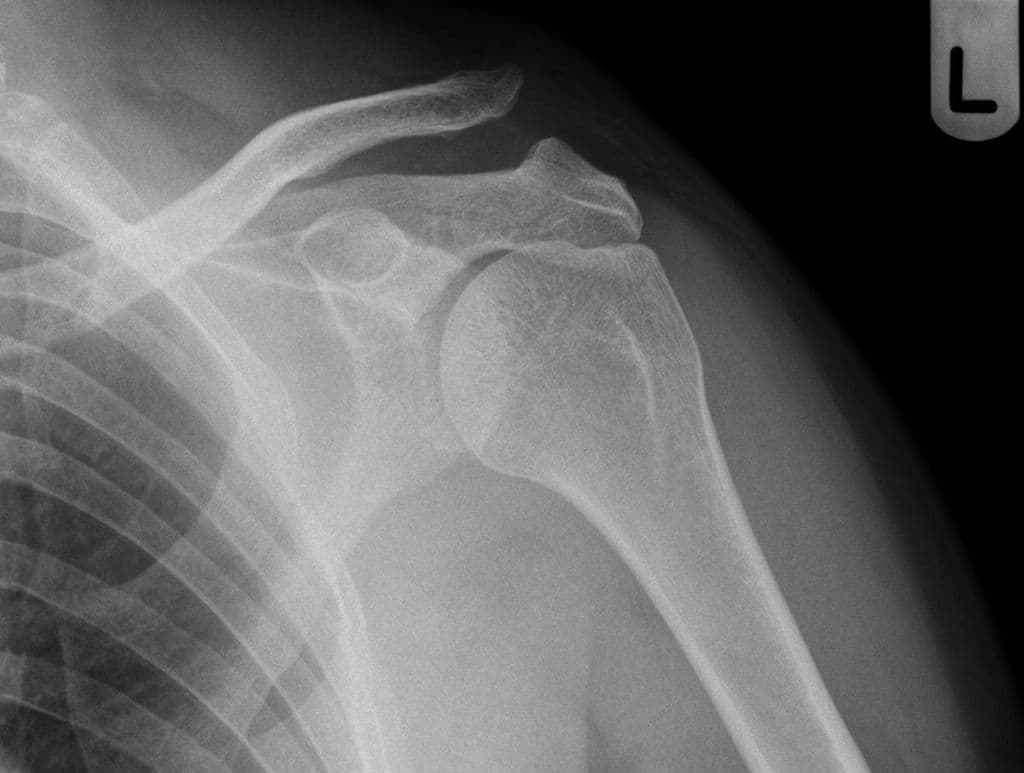

Đau khớp vai phải, sốt

- Có các ổ dịch ngấm thuốc viền (peripherally enhancing collections) xung quanh khớp cùng đòn mỏm cùng phải.

- Các ổ này đi kèm với tín hiệu bất thường ở tủy xương trong mỏm cùng (acromion) và đầu xương đòn (distal clavicle), cùng với các ổ ăn mòn vỏ xương (cortical erosions) ở xương đòn.

Acromioclavicular Joint Dislocation (Trật khớp cùng đòn)